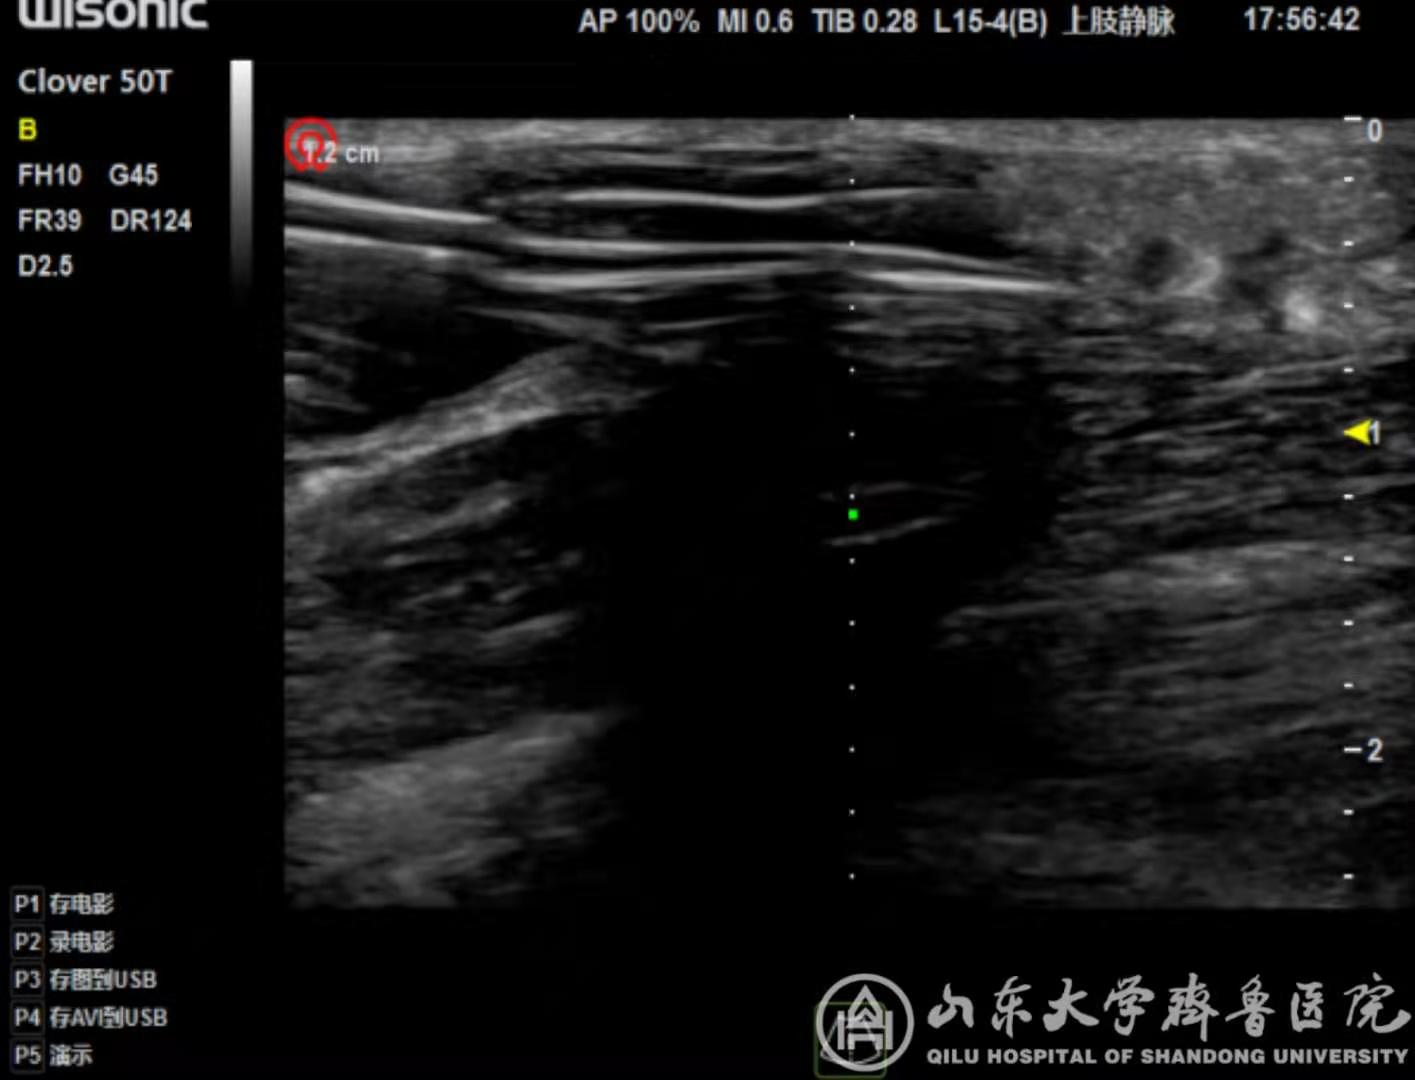

目前随着透析患者数目的增多和透析技术的进步,透析患者生存期逐渐延长,因此构建可长期使用的血管通路是对于透析患者长期生存至关重要的问题。由于血管本身的变异,加之很多肾衰患者合并高血压及糖尿病,有部分患者血管条件差,不存在建立自体内瘘的条件,因此人工血管(AVG)是该类患者重要的重要通路。但人工血管并非自体结构,存在血栓、狭窄等可能性亦较自体血管的概率高,一旦出现血栓,人工血管将失去功能,需要紧急开通。即穿型人工血管有三层结构,若无B超引导盲目穿刺,可能穿到中层或后壁,风险较正常偏高。相较传统手术方式,B超引导腔内开通术具有患者损伤少,见效快,无放射损伤等优势。

清晰的B超影像为手术提供了精确指引

近期完成的两例B超引导下即穿性人工血管腔内PTA开通手术,该类手术可日间完成,手术后可即时使用,避免过度期插管,处于省内先进水平,标志着我院对AVG有良好的维护能力,为广大肾衰患者健康带来了福音。